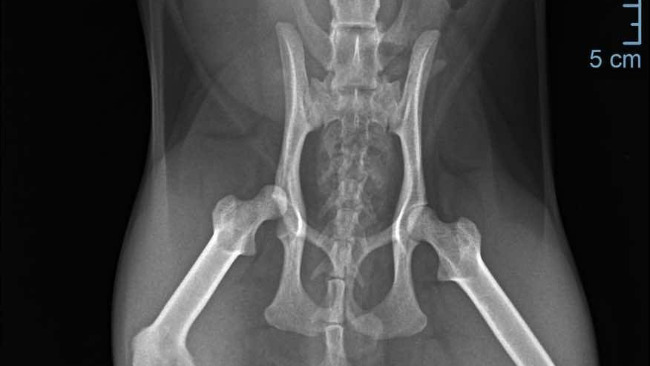

Miała wstrząs, przecięty język, a ból w jej oczach mówił więcej niż tysiąc słów.Po wykonaniu RTG okazało się, że ma zwichnięty staw biodrowy, który wymaga pilnej operacji. Jej koszt to 1500 zł. Do tego rehabilitacja…